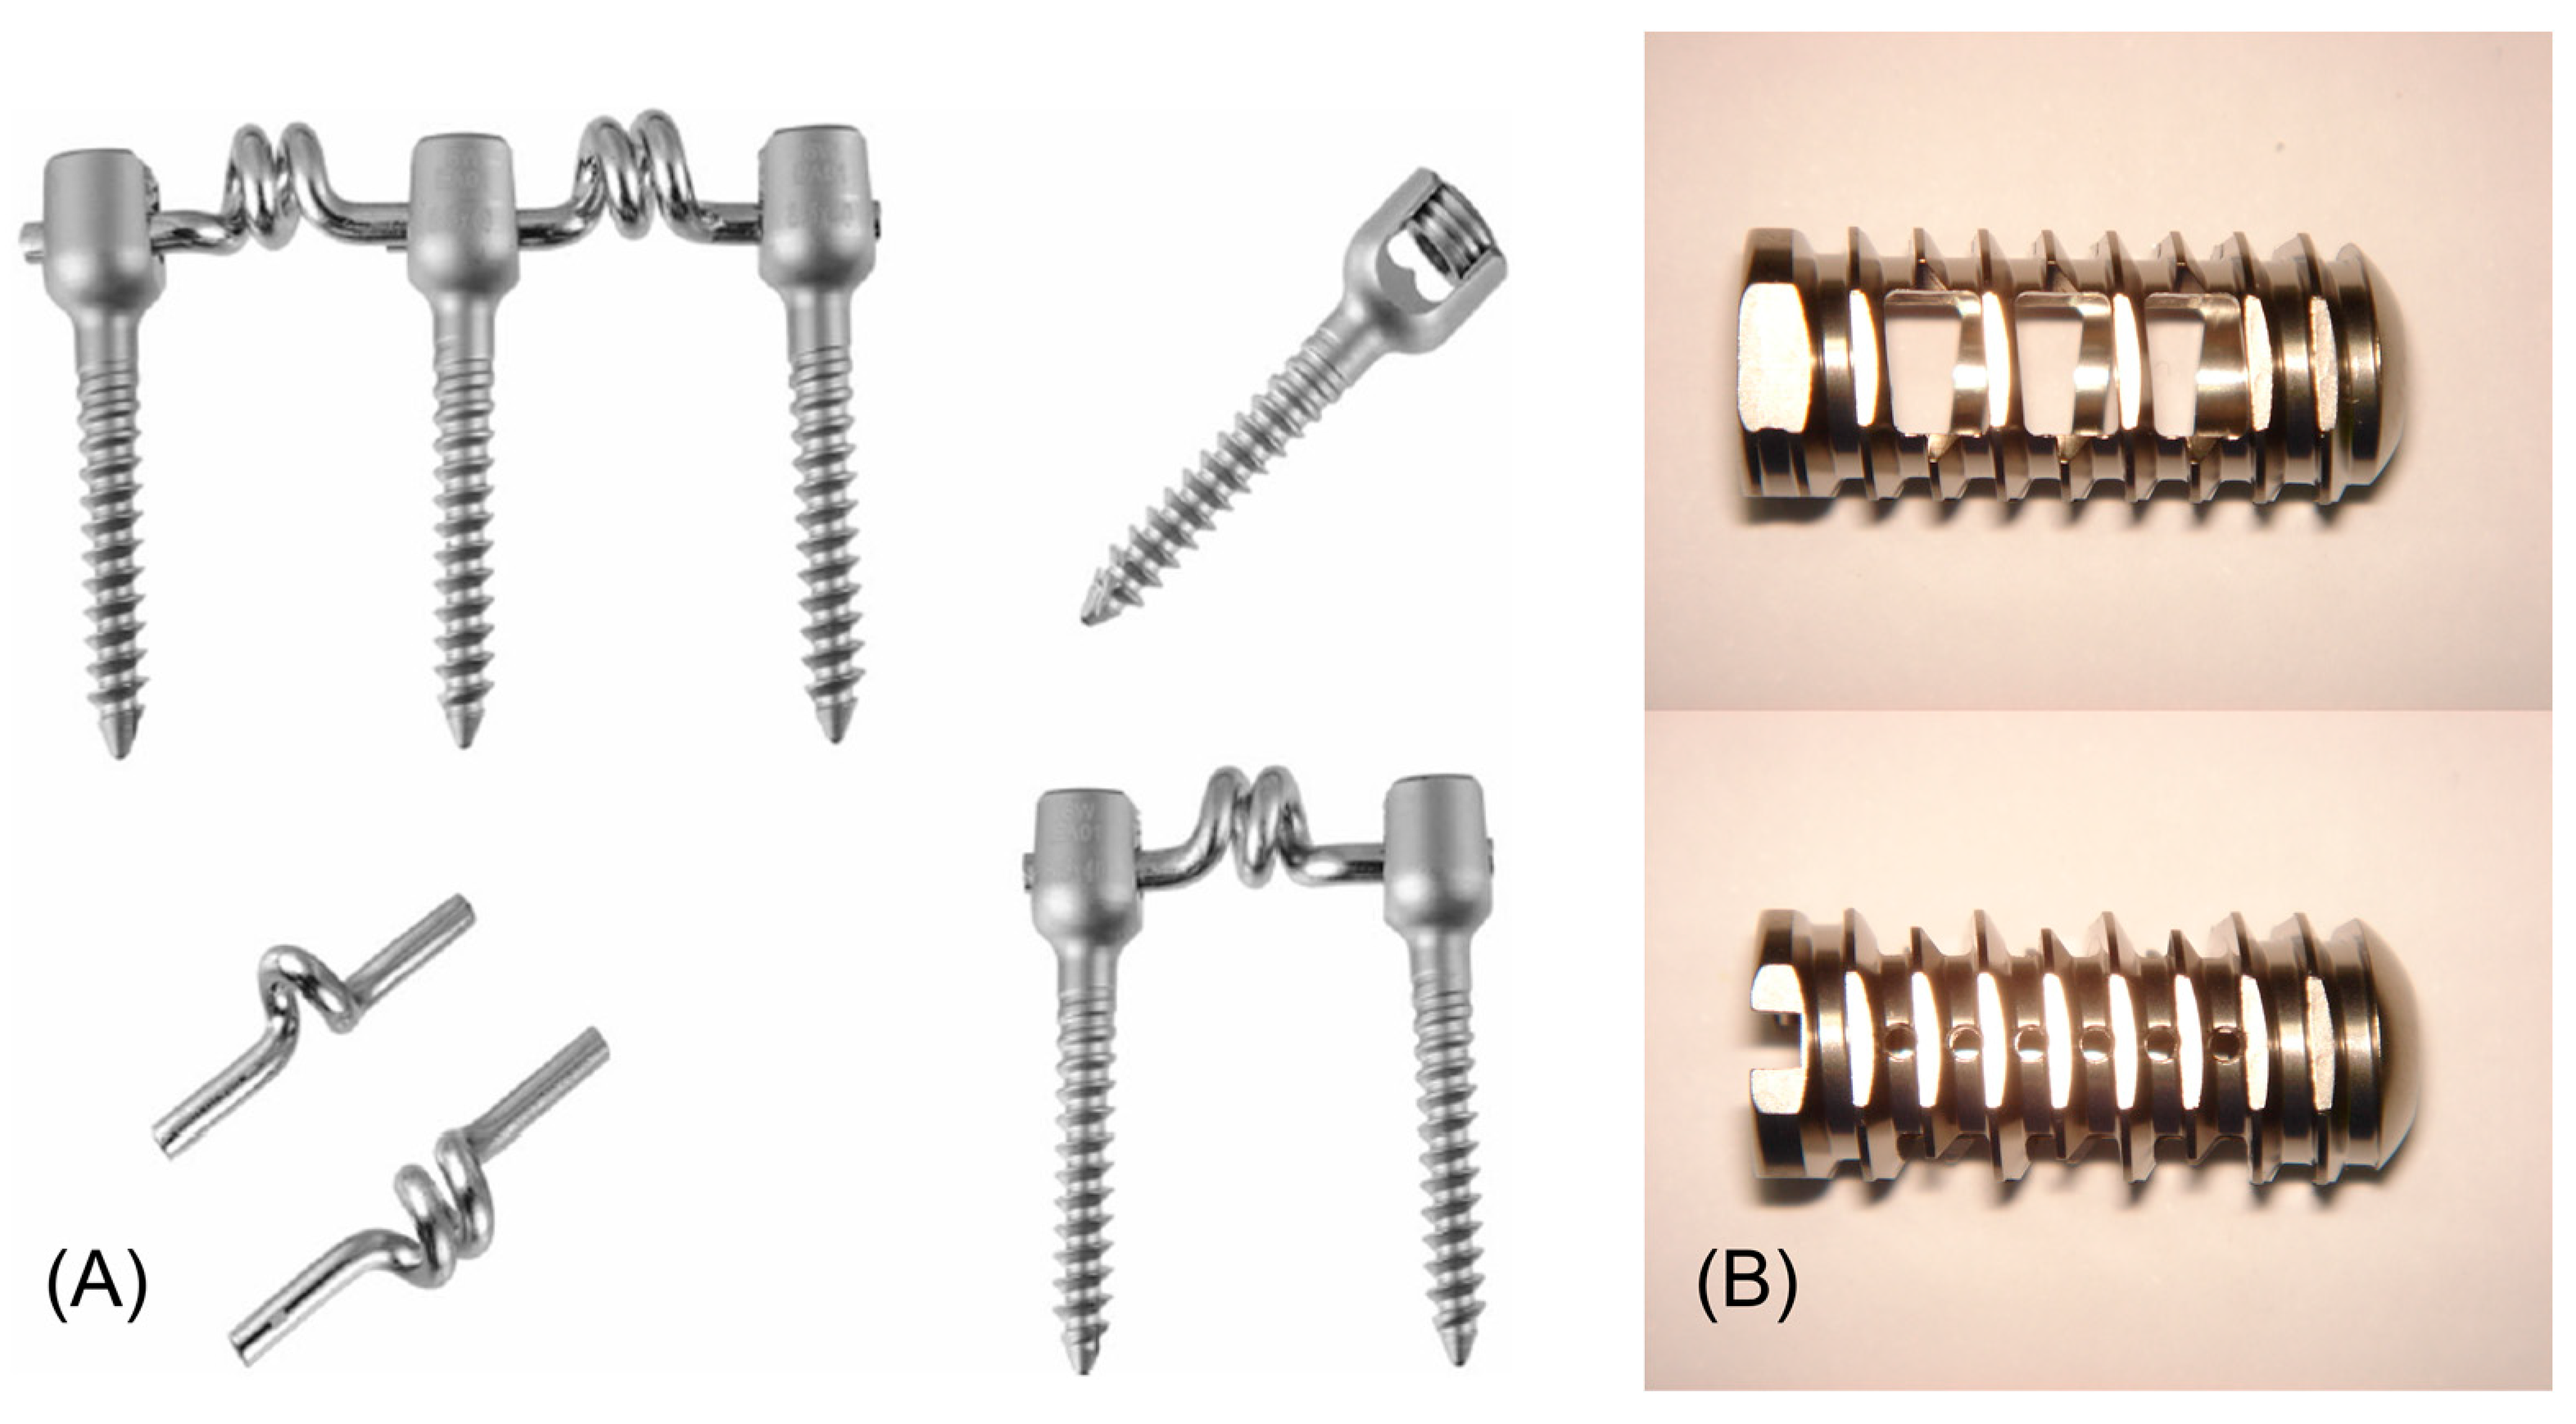

- Zhang, H.Y.; Park, J.Y.; Cho, B.Y. The Bioflex System as a Dynamic Stabilization Device: Does It Preserve Lumbar Motion? J. Korean Neurosurg. Soc. 2009, 46, 431. [Google Scholar] [CrossRef]

- Kim, Y.-S.; Zhang, H.-Y.; Moon, B.-J.; Park, K.-W.; Ji, K.-Y.; Lee, W.-C.; Oh, K.-S.; Ryu, G.-U.; Kim, D.H. Nitinol Spring Rod Dynamic Stabilization System and Nitinol Memory Loops in Surgical Treatment for Lumbar Disc Disorders: Short-Term Follow Up. Neurosurg. Focus. 2007, 22, 1–9. [Google Scholar] [CrossRef]

- Massey, P.A.; Hoge, S.; Nelson, B.G.; Ogden, A.L.; Mody, M.G.; Myers, M.; Bilderback, K.; Solitro, G.; Barton, R.S. Nitinol Memory Rods Versus Titanium Rods: A Biomechanical Comparison of Posterior Spinal Instrumentation in a Synthetic Corpectomy Model. Glob. Spine J. 2021, 11, 277–282. [Google Scholar] [CrossRef] [PubMed]